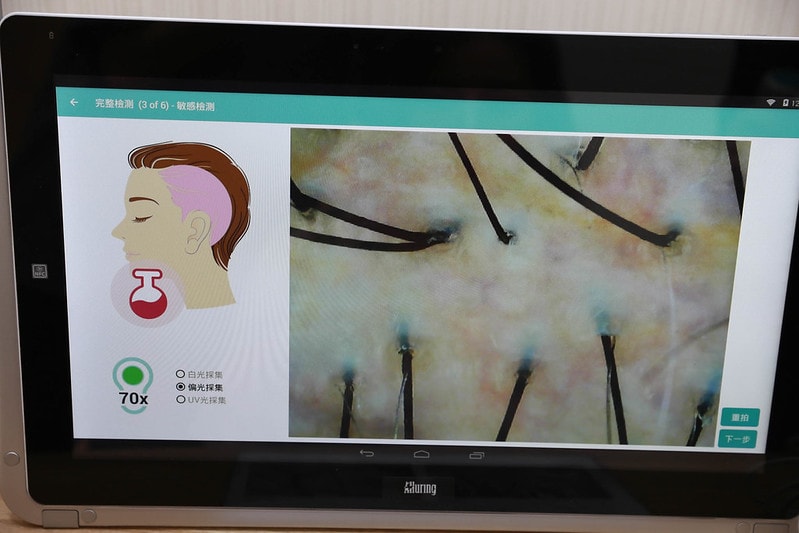

這部分真是讓我最訝異了

可以放大更細微的地方查看

紅色部分就有可能是細菌比較容易孳生的部位

一定要徹底保養才不會讓頭皮也變成細菌孳生的溫床